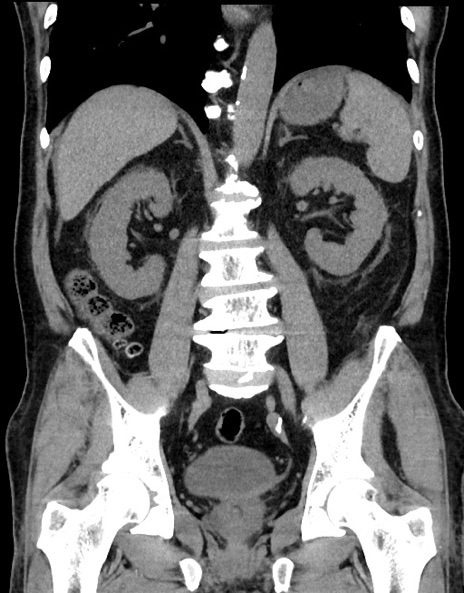

横断像

【症例】70歳代男性

【主訴】腹痛

【現病歴】今朝から腹痛あり。全体的に痛い。特に左上の方。排ガスが今日はない。冷や汗が出る。

【既往歴】直腸癌術後

【身体所見】左側腹部〜上腹部に圧痛あり。腹膜刺激症状明らかなではない。軽度反跳痛。左下腹部に術後瘢痕あり。

【データ】WBC 7700、CRP 0.02